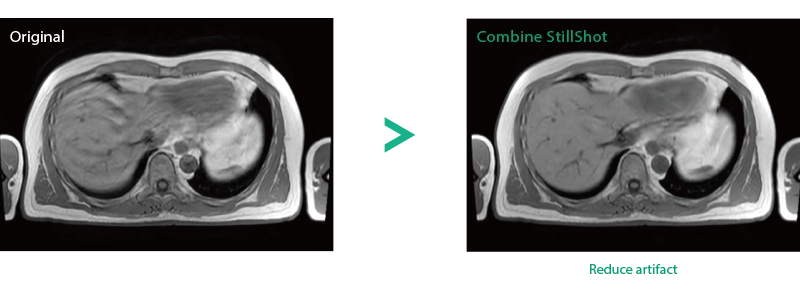

Reduce artifacts caused by patient movement, such as coughing or sneezing, by post reconstruction.

When motion artifacts occurs in the image due to coughing, sneezing, or involuntary movements, either or both the visual information acquired by monitoring cameras, Synergy Vision, and the intrabody information acquired by the navigator pulse can be used to provide an image with reduced artifacts. This reduces the re-imaging rate.

Body movements that affect image quality are detected from monitoring cameras based on thresholds derived for each body part.